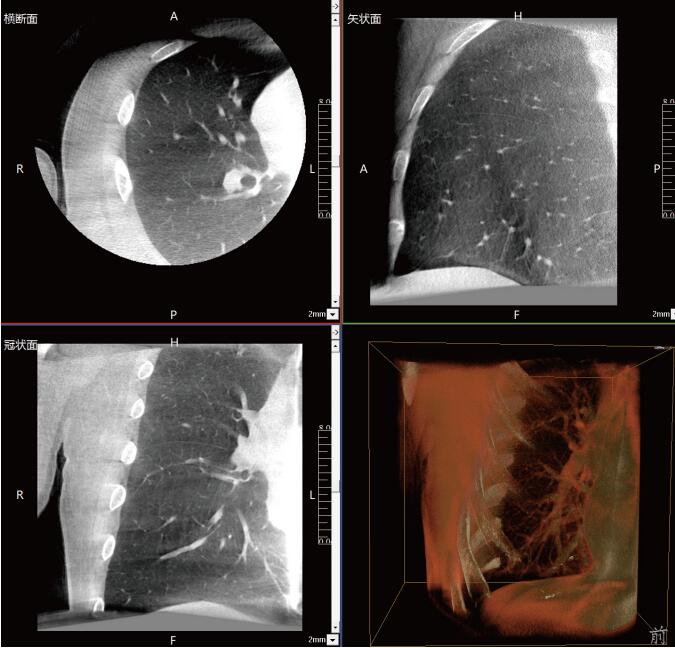

大功率平板三維C形臂PLX C7600術(shù)中實(shí)時(shí)生成:橫斷面、矢狀面、冠狀面及三維影像,可在任意切面、任意角度評(píng)估植入物和解剖結(jié)構(gòu)的相對(duì)位置,在手術(shù)室中即可完成結(jié)果的檢查確認(rèn),適用于全身各個(gè)部位。

一站式“術(shù)中CT”,肺部診斷+治療新選擇

常規(guī)流程下需要術(shù)前CT室內(nèi)的引導(dǎo)定位,再轉(zhuǎn)入手術(shù)室進(jìn)行胸腔鏡手術(shù),在轉(zhuǎn)運(yùn)過(guò)程中有氣胸、肺出血和導(dǎo)針脫落的風(fēng)險(xiǎn)。使用大功率平板三維C形臂PLX C7600,可在手術(shù)室內(nèi)一站式完成肺部三維影像重建,在穩(wěn)定呼吸的條件下,亞亳米級(jí)定位肺結(jié)節(jié)位置,有效規(guī)避穿刺路徑附近的血管、氣管等重要解剖結(jié)構(gòu),術(shù)中確保穿刺安全有效。同時(shí)可大幅降低輻射劑量,減少射線對(duì)醫(yī)患的傷害。